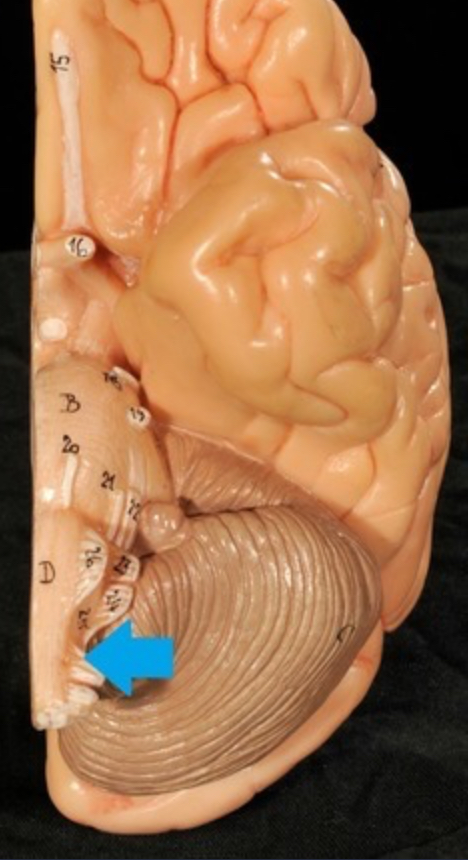

Cerebellum